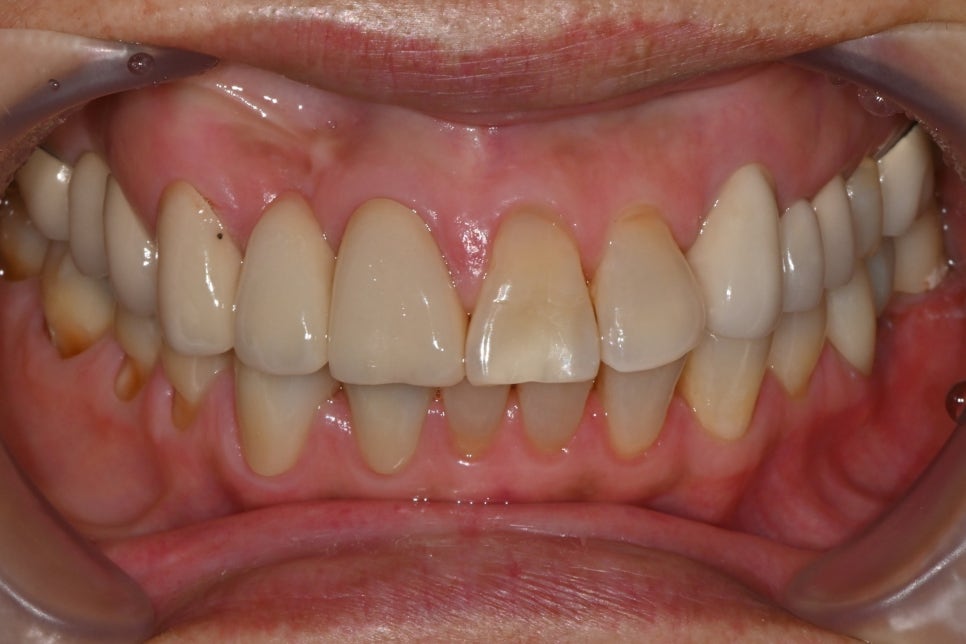

➤ Initial examination findings

Before planning the aesthetic front tooth prosthetics and molar implant treatment, here is the patient's initial condition.

After a comprehensive diagnosis of tooth alignment, missing areas, and the condition of existing prosthetics, the following treatment plan was explained:

Right lower molar area (#45~47): We recommended removing the old bridge and making new crowns for #45 and #47, and for the empty space at #46, we recommended placing one implant instead of the existing bridge.

Front tooth area (#11): There was severe cervical wear, and additional prosthetic treatment was needed.

Lower front tooth area (#43, #42): The space between the teeth had widened, so we planned an aesthetic improvement using crowns.

Intraoral photos at the first visit